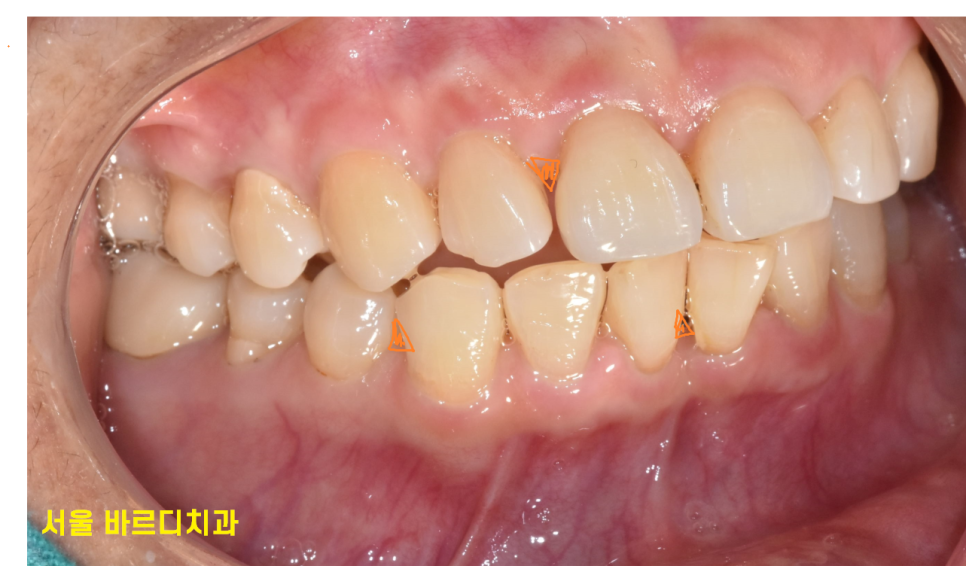

노화로 인해 치아가 조금씩 이동하거나

잇몸이 약해지면서 간격이 벌어져 음식물이 더 자주 끼게 됩니다!

치아 사이 공간 더 커집니다.

반복적으로 이쑤시개를 사용하면

치아와 치아 사이의 틈이 더 벌어질 수 있습니다.

이는 음식물 끼임을 더욱 악화시키는 악순환이 반복되게 됩니다.